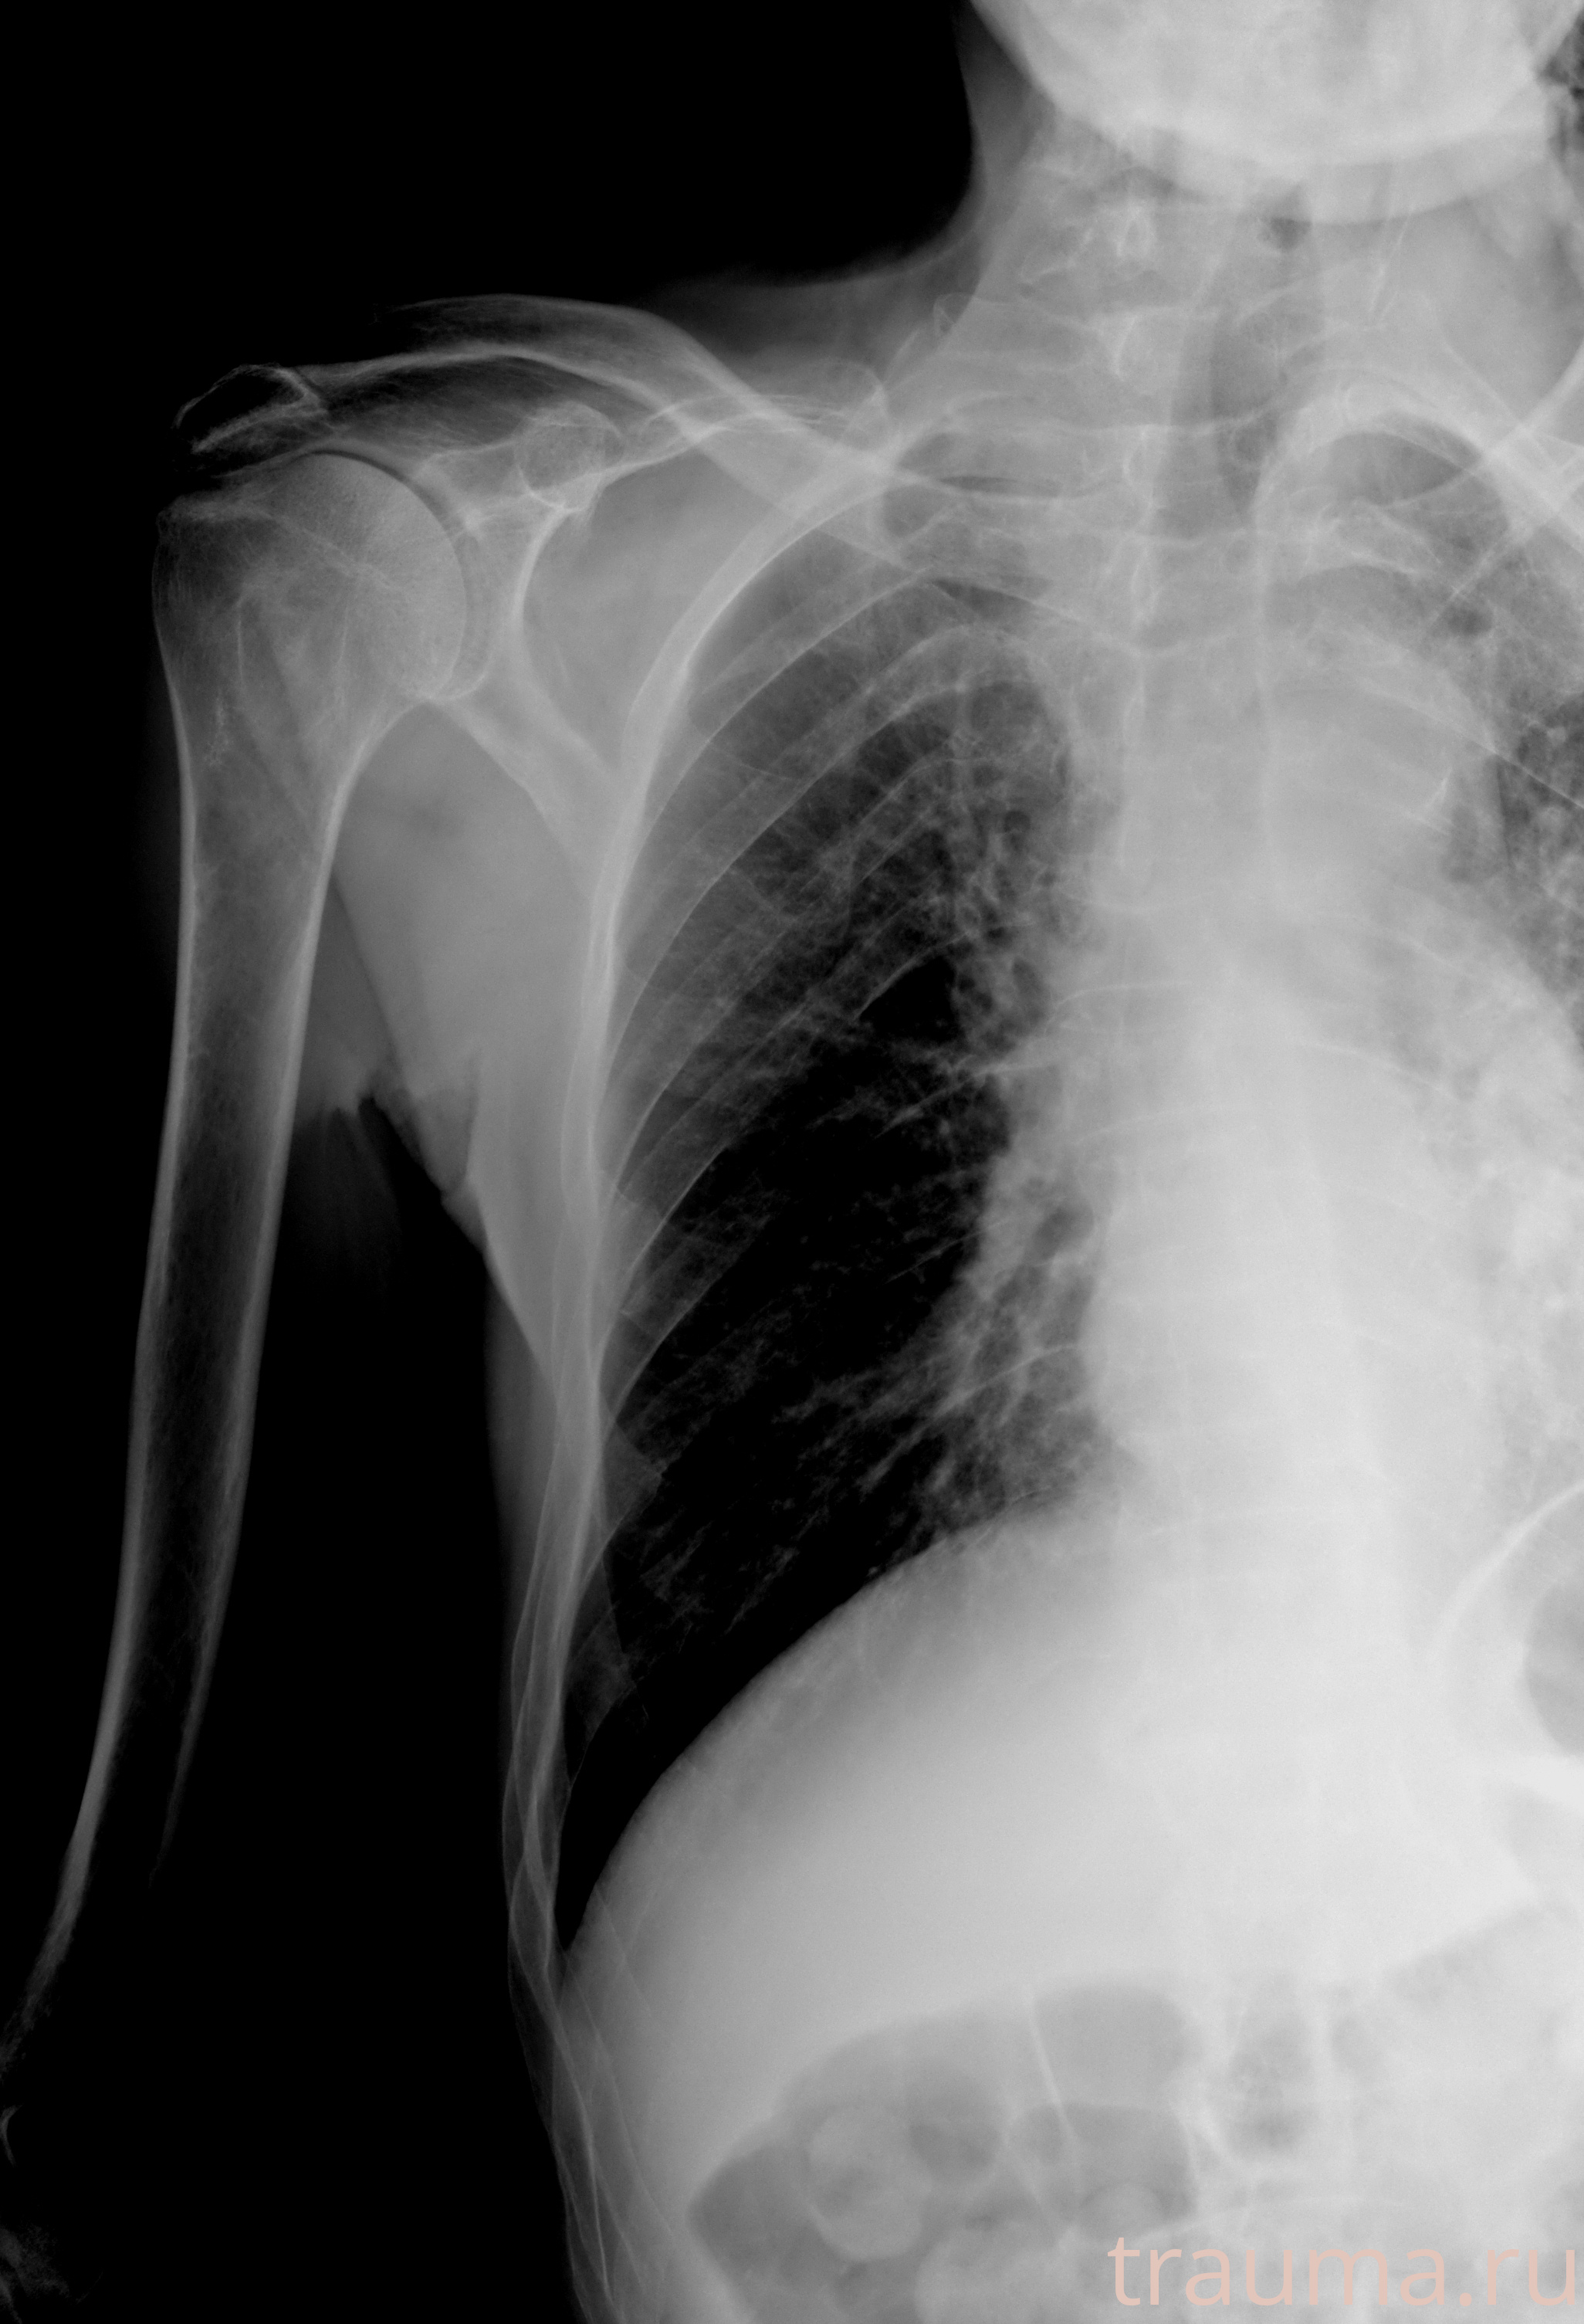

Рентгенограммы

Рентген на дому: по вашему адресу приезжает врач-рентгенолог, травматолог-ортопед с мобильным рентгеновским аппаратом, проводит диагностику травмы или заболевания, делает необходимые рентгенограммы, дает рекомендации по дальнейшему лечению. Получить качественные снимки в домашних условиях возможно благодаря уникальной методике, разработанной МосРентген Центром для института  Склифосовского

при переломе шейки бедра и пневмонии от компании МосРентген Центр - партнера Института имени Склифосовского